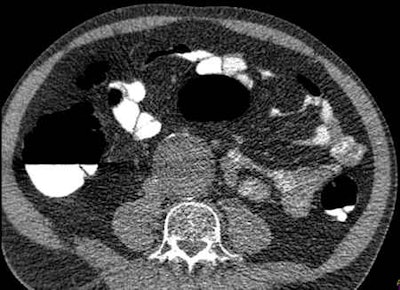

| Image shows a large abdominal aortic aneurysm, which is a relatively easily detectable and common possibly important finding. Image courtesy of Dr. Thierry Boellaard. |